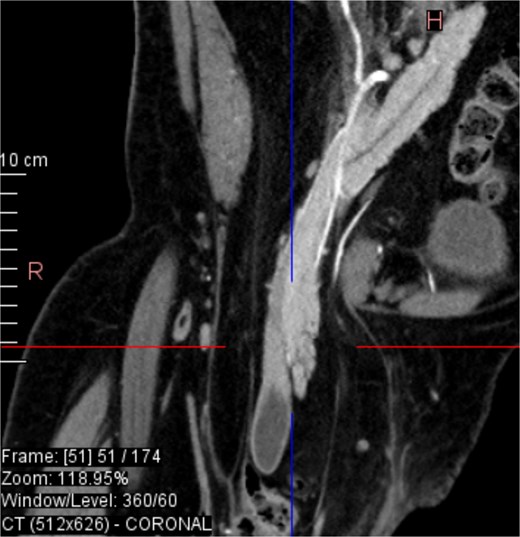

From the provided coronal CT image (Fig. 1), the following findings are noted: The spinal curvature is prominently right-convex in the lumbar region, indicating a dextroscoliosis with marked rotation of vertebral bodies, causing asymmetrical displacement of the retroperitoneal organs. The curvature shortens the abdominal cavity vertically on the left side, while expanding the retroperitoneal volume on the right. The right femoral head is elevated and laterally displaced, consistent with developmental dysplasia of the hip. There is flattening of the acetabulum and apparent false articulation with the iliac wing. These findings suggest chronic alteration of pelvic symmetry with pelvic tilt and subsequent uneven distribution of abdominal and intra-pelvic pressure. The combined effects of spinal curvature and pelvic deformity create an aberrant vector of force and organ positioning, contributing to the downward displacement of the pancreas and duodenum.

CT imaging (Figs 2–5) revealed a right inguinal hernia containing small bowel loops, ascending colon, the second and third portions of the duodenum, and the pancreatic head. The pancreatic head appeared rotated and displaced inferiorly into the hernia sac, without signs of acute pancreatitis.

Dextroscoliosis with marked rotation of vertebral bodies, displaced right femoral head and giant inguinal hernia.

Coronal CT view inguinal hernial sac with pancreatic head and D2 and D3 segment of duodenum.